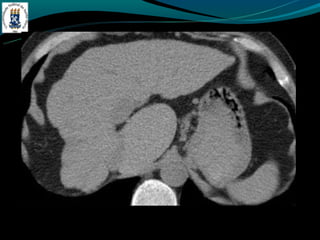

BUDD-CHIARI

-Hipercoagulabilidade

-Compressão – tumor

-Membrana da VCI

-Dor abdominal, hepatomegalia e ascite.

- TC: hepatomegalia heterogênea, não visualização das veias

hepática, ascite, realce hepático central, lobo caudado preservado

ou aumentado.

BUDD-CHIARI -Hipercoagulabilidade -Compressão – tumor -Membranada VCI -Dor abdominal, hepatomegalia e ascite. - TC: hepatomegalia heterogênea, não visualização das veias hepática, ascite, realce hepático central, lobo caudado preservado ou aumentado.